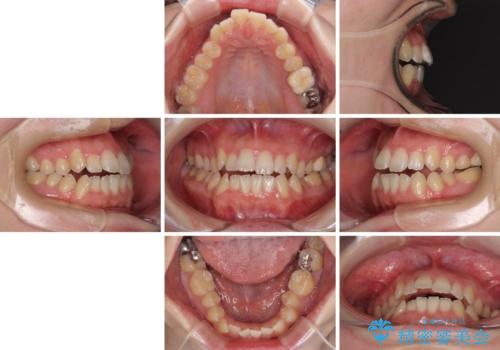

オープンバイトと前歯のデコボコをインビザライン矯正で解消

- 前歯の開咬を気にして来院された患者様です。

開咬の治療は、前歯を閉じるように動かすとともに、上下臼歯を圧下(骨内にめり込ませる)させることで進めて行きます。

インビザラインは臼歯の圧下を効果的に行えるため、インビザラインを用いて矯正治療を行うこととしました。